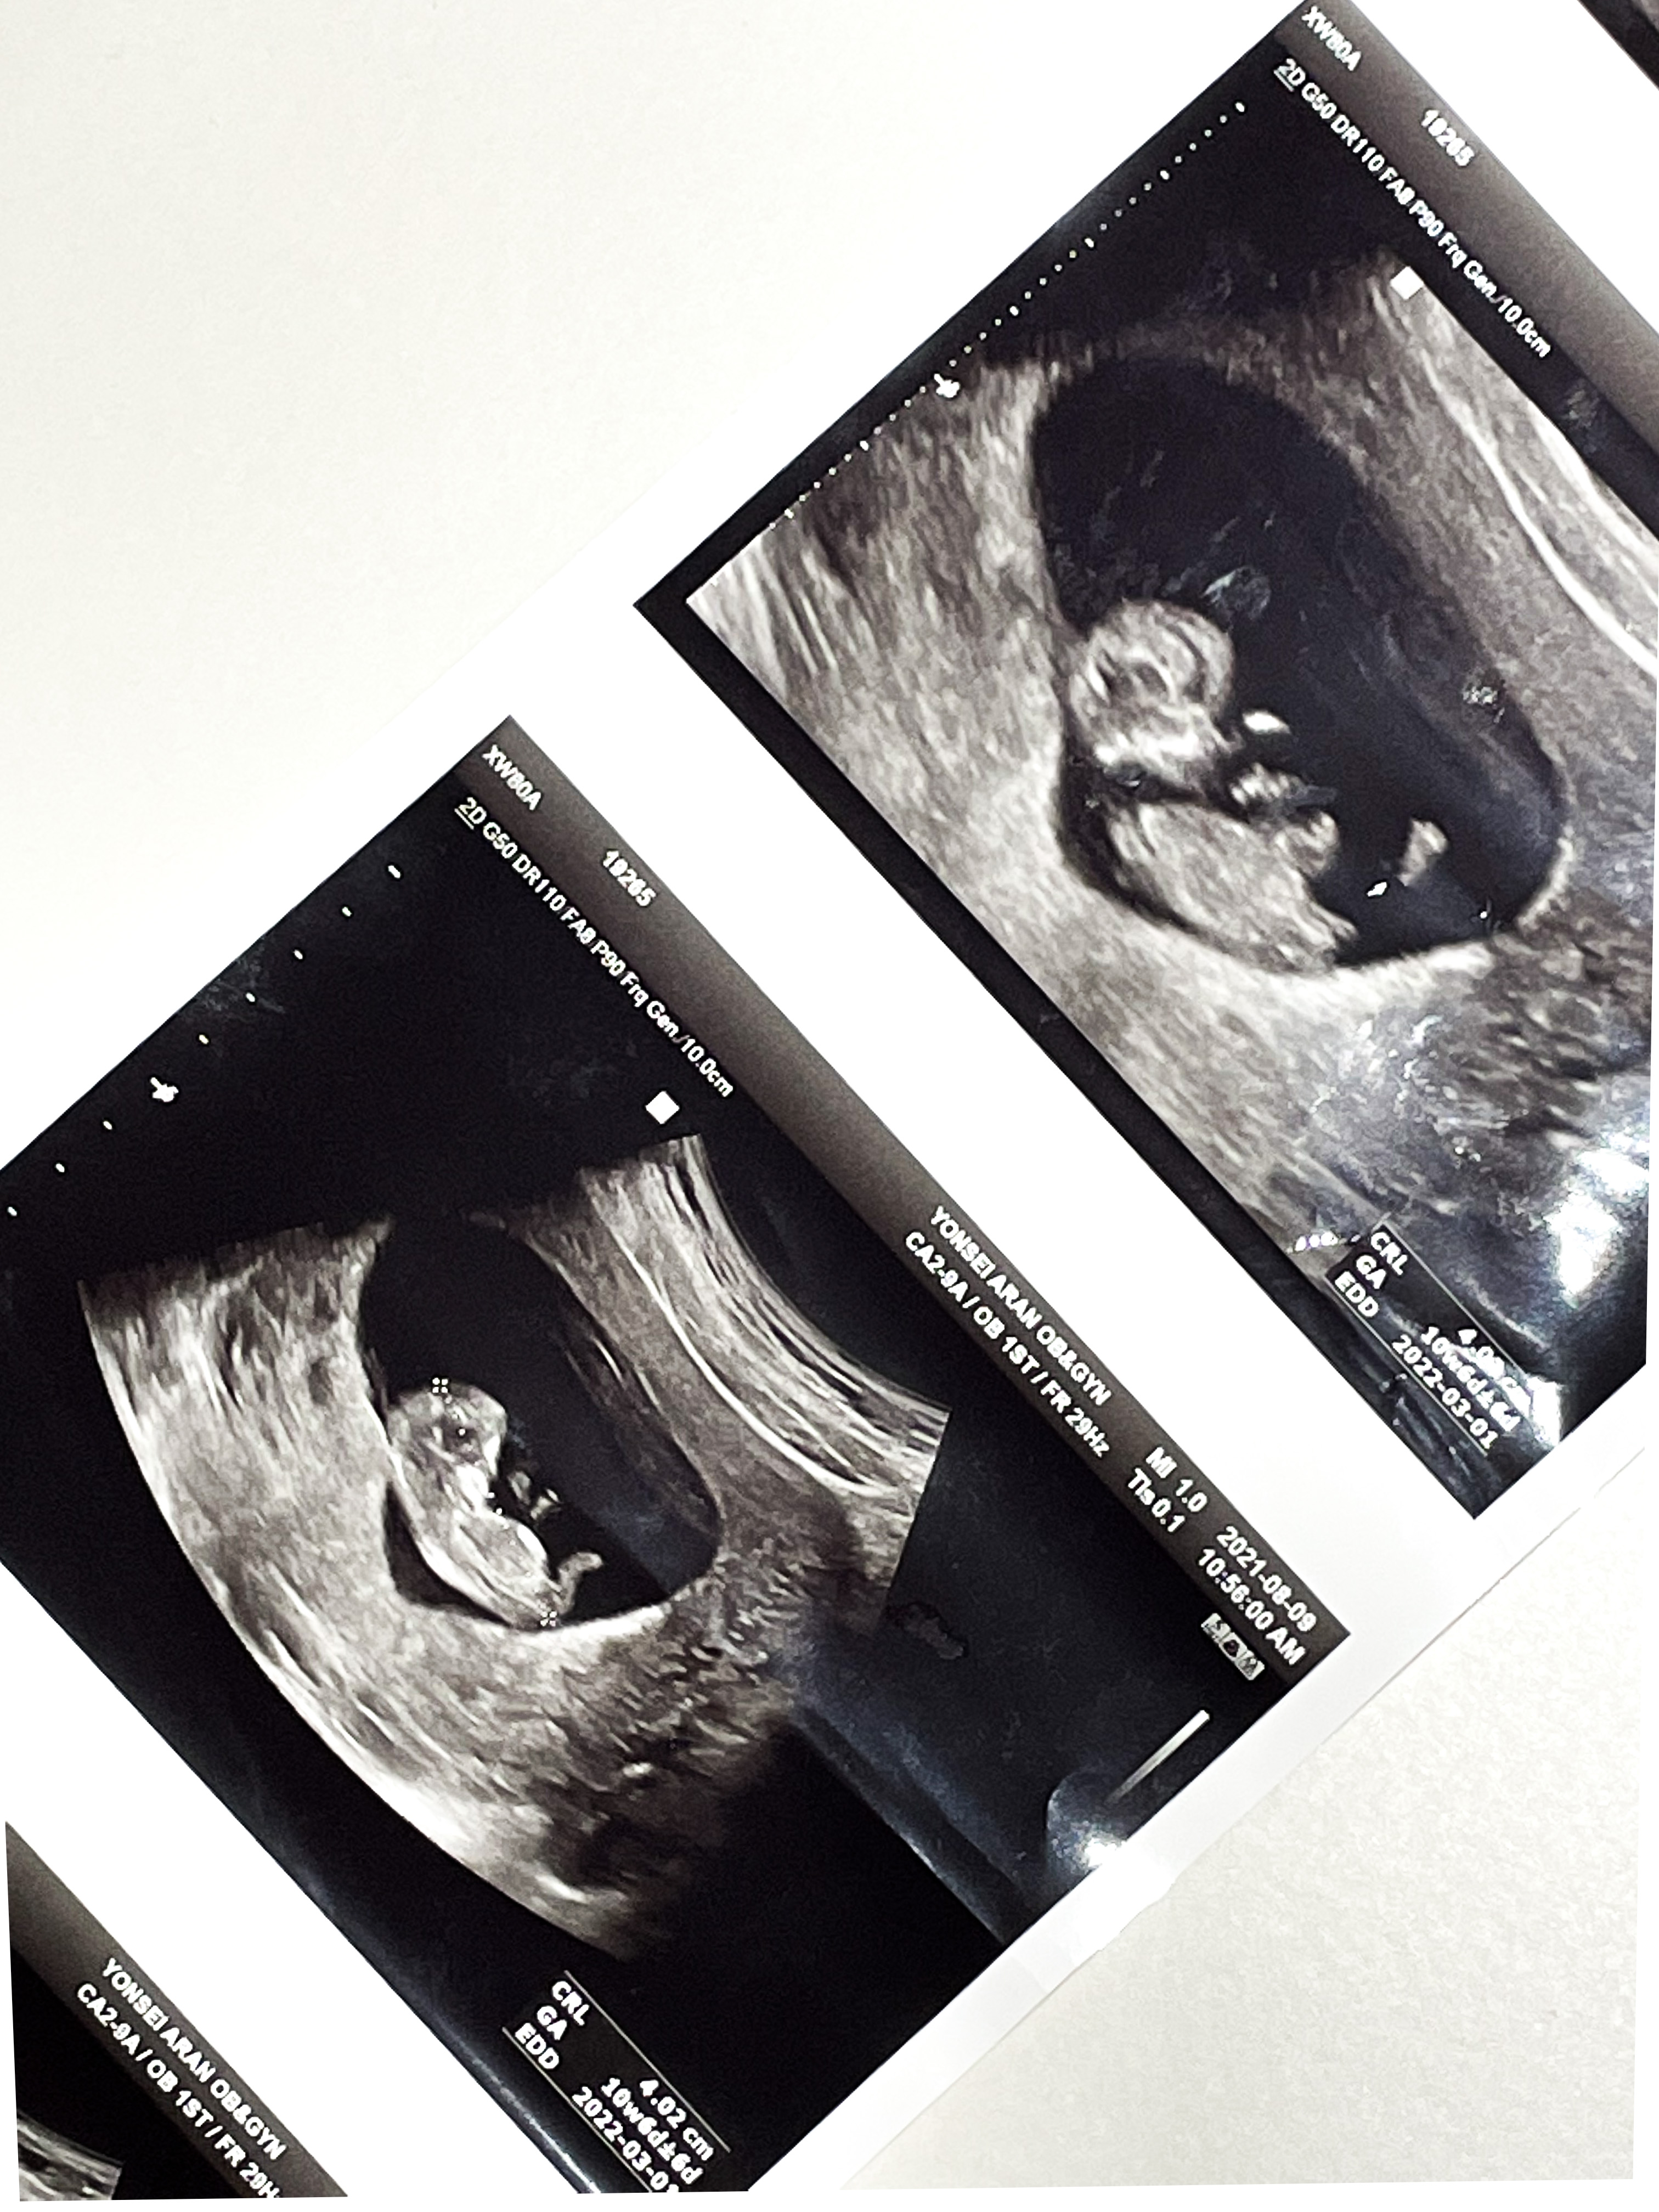

10주 4일

벌써 배초음파를 볼 수 있었다.

2주사이에 배도 더 통통해지고

코도 보였다.

쌤이 코가 높다고 해주셔서 기분이 좋아졌다.

발바닥도 보인다고 찍어주셨는데

발바닥이 넘나 귀여웠다.

팔다리도 길쭉 해지고,

아주 기특하게 잘 자라고 있었다.